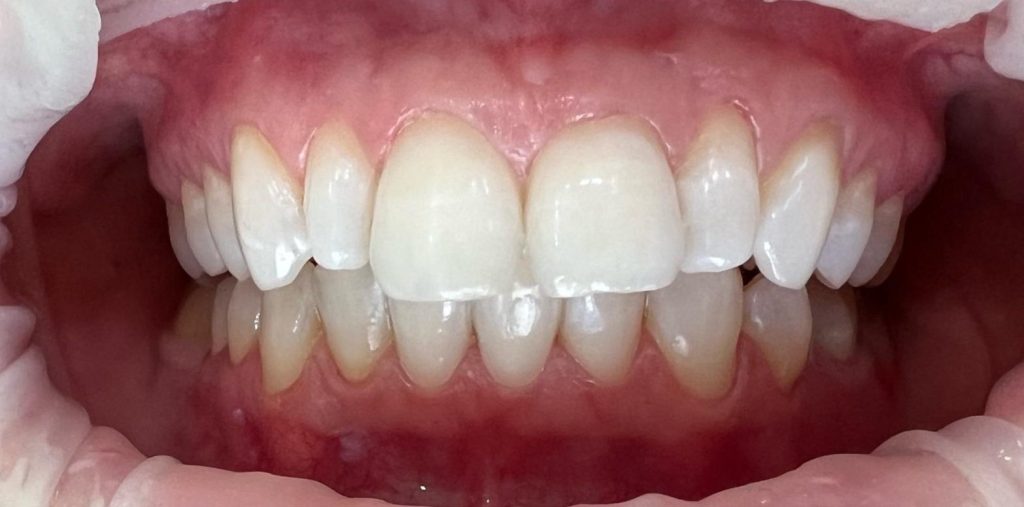

Pod kierownictwem lek. stom. Michała Badowskiego po wnikliwej analizie została przeprowadzona korekta dziąseł i pozbycie się nieestetycznych koron na podbudowie metalowej, eliminując tym samym nawracające stany zapalne dziąseł.

Następnie została wykonana wizualizacja nowego uśmiechu, idealnie dopasowana do twarzy Pacjentki. Po jej akceptacji, przygotowaliśmy komplet koron i licówek pełnoceramicznych na górne i dolne zęby.

Całe leczenie trwało zaledwie 3 miesiące!

Dzięki współpracy lek. stom. Michała Badowskiego i techn. dent. Joanny Gancarz z laboratorium Dentalscan Pacjentka zachwyca pięknym uśmiechem!